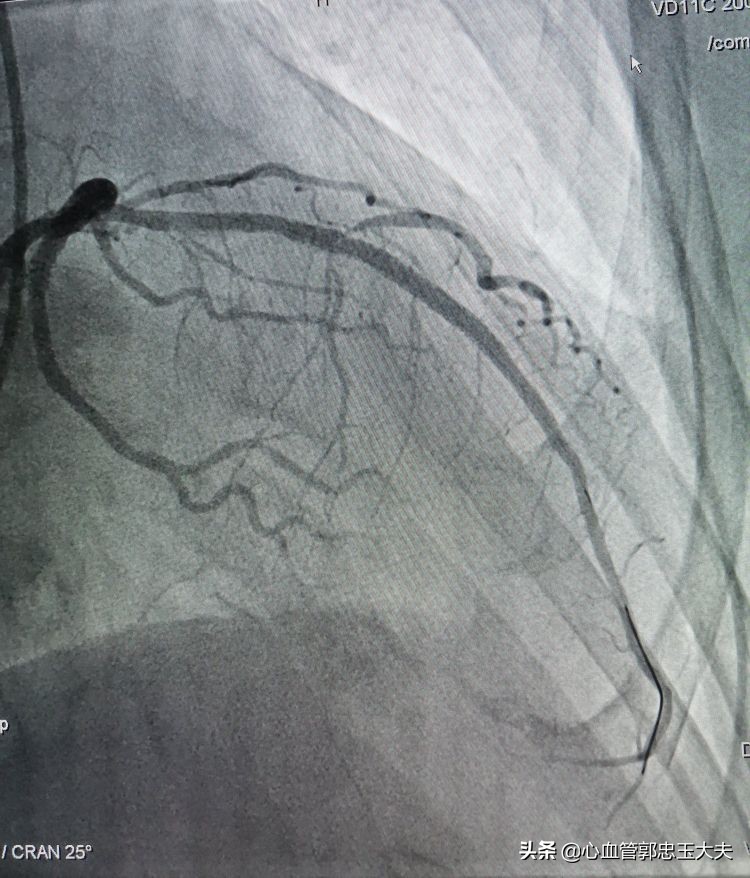

支架植入后,在回旋支再次预埋球囊,扩张后支撑力明显加强,微球囊通过闭塞病变,扩开闭塞血管。最后前降支植入支架,影像效果满意(如下图)